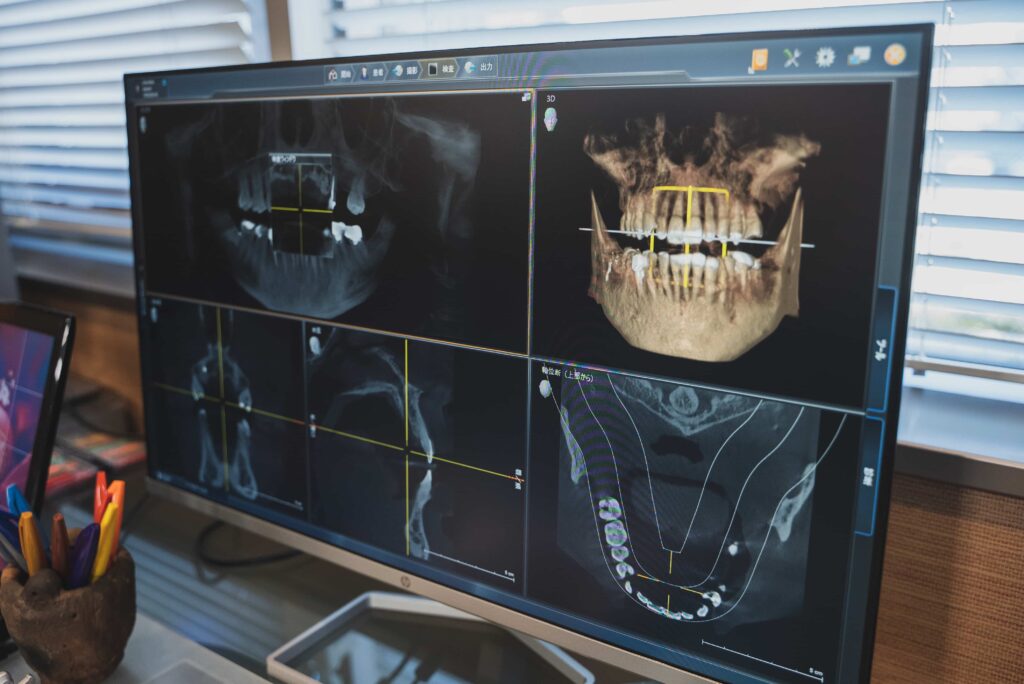

CT・シミュレーションなど先進設備による治療

先進設備・技術を導入し、治療の効率化や患者さまの負担軽減を図っているのも当院の特徴です。無菌治療室はもちろん、被ばく線量を1/100〜1/300に軽減できる頭部専用の最新CTスキャンを導入しています。

インプラント用の3Dシミュレーションシステムにより、手術模型からインプラントガイドを作成することで、即日で仮歯の装着も可能です。最新のマイクロスコープも、精密な治療の実現に貢献しています。